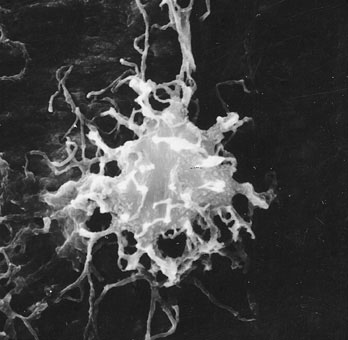

60. Comparazione tra forma e dimensione degli osteociti. Si noti la loro diversa forma:globosa nell'ossoa fibre intrecciate (A); allungata, mandorliforme, nell'osso lamellare (B);allungata,elissoidale, nell'osso a fibre parallele (C). Femore (Homo).